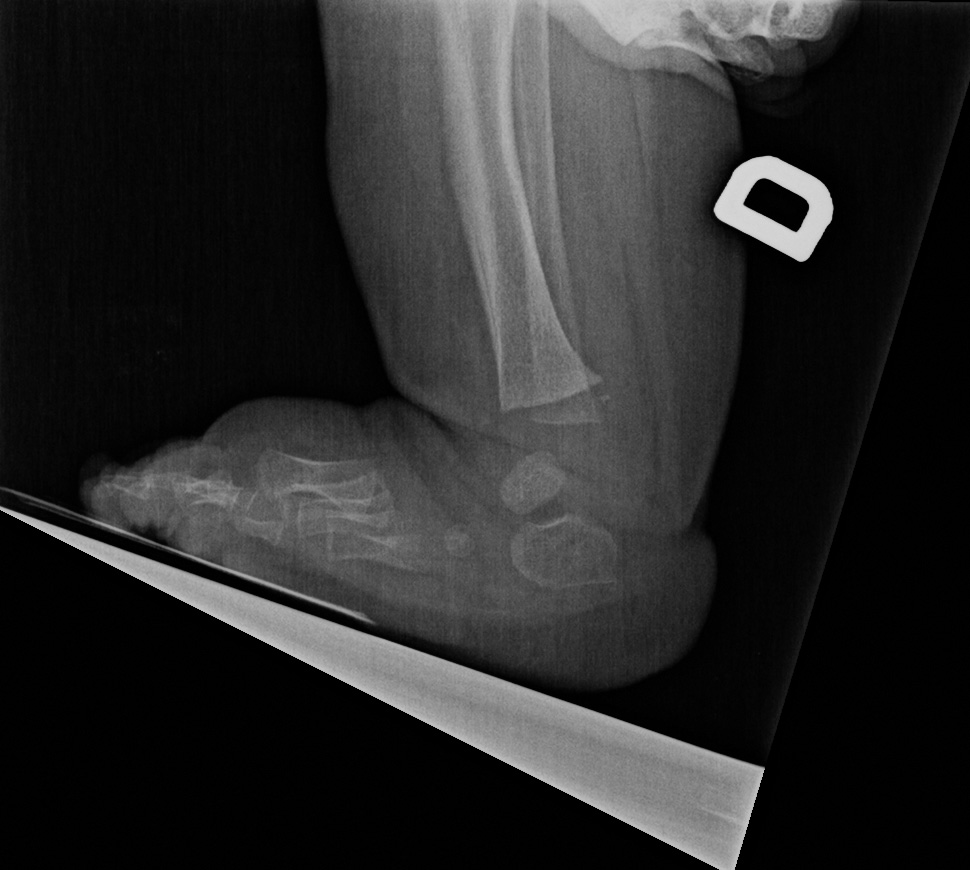

0-hour-old male:

Feet deformity.

On the right side, the anteroposterior talo-calcaneal angle (Kite's angle) is decreased to 7° (normal between 20 and 40°). On the lateral view of Turco, the talo-calcaneal angle is 30° (normal over 35°). In short, on the anteroposterior view, the talus and calcaneus are more parallel than expected (normaly they are diverging).

On the right anteroposterior view, the talus-1st metatarsal angle is measured at -7° (normal between 0 and 20°). The 1st metatarsal is medial to the talus because of the forefoot deviation in varus and adductus.

On the left side, the talus is not ossified enough to take measurements. Global alignment, however, suggests a left club foot of similar severity than the right.